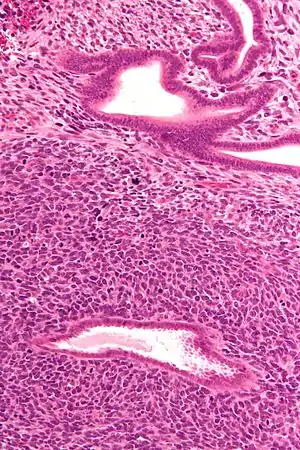

| Micrograph of a uterine adenosarcoma showing a mitotically active malignant stroma and benign glands. H&E stain. | |

Uterine adenosarcoma have, by definition, a malignant stroma and benign glandular elements. The World Health Organization (WHO) criteria have a mitotic rate cut point; however, this is often disregarded, as bland-appearing tumours with a low mitotic rate are known to metastasize occasionally.[2]